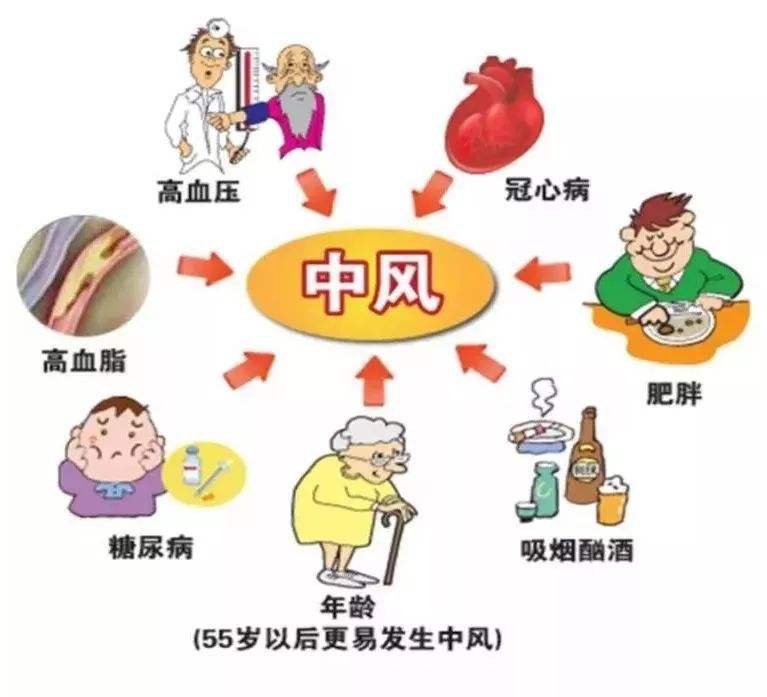

中風(fēng)

如(rú)果您有(yǒu)睡(shuì)眠呼吸暫停,持續使用(yòng)C PAP可(kě)以降低(dī)中風(fēng)的(de)風(fēng)險,中風(fēng)是(shì)導緻死亡和(hé)長(cháng)期殘疾的ε(de)主要(yào)原因之一(yī)。中風(fēng)是(shì)腦(nǎo)功能(néng)突然喪失。它發生(shēng)在通(tōng)向大(dà)腦(nǎo)的(de)血管之一(yī)發生€(shēng)阻塞或破裂時(shí)。睡(shuì)眠呼吸暫停未經治療的(de)人(rén)中風(fēng)的(de)可(kě)能(néng)性要(yàδo)高(gāo)兩到(dào)四倍。

PAP可(kě)以降低(dī)中風(fēng)的(de)風(fēng)險,中風(fēng)是(shì)導緻死亡和(hé)長(cháng)期殘疾的ε(de)主要(yào)原因之一(yī)。中風(fēng)是(shì)腦(nǎo)功能(néng)突然喪失。它發生(shēng)在通(tōng)向大(dà)腦(nǎo)的(de)血管之一(yī)發生€(shēng)阻塞或破裂時(shí)。睡(shuì)眠呼吸暫停未經治療的(de)人(rén)中風(fēng)的(de)可(kě)能(néng)性要(yàδo)高(gāo)兩到(dào)四倍。